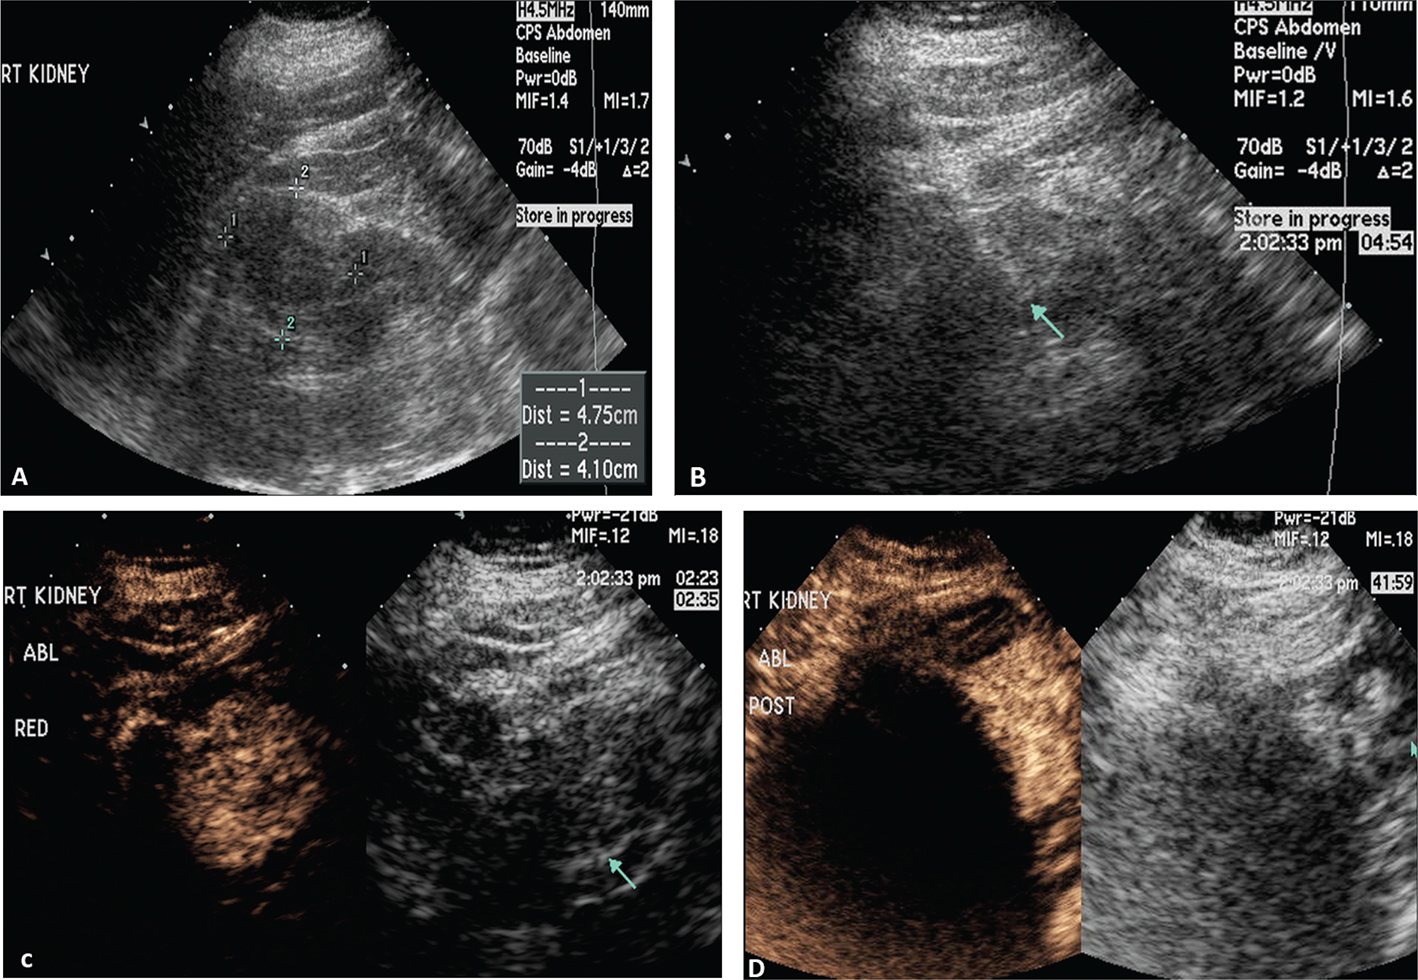

Figure 1 demonstrates the steps in performing a CEUS RFA. Figure 1A is the unenhanced B-mode US before the procedure. In this case, the mass is easily identified. If the mass is not visualized well, a CEUS can be performed to confirm the size and location of the mass. Figure 1B shows the position of the RFA needle in the mass. Figure 1C is the image after the injection of the ultrasound contrast confirming the position of the needle in the mass. Figure 1D shows that there is no flow remaining in the renal mass, confirming complete ablation of the lesion.

Figure 1. Images demonstrating RFA of an RCC. (A) B-mode image of the RCC (calipers) pre-procedure, (B) B-mode image demonstrating positioning of the RFA needle (arrow) in the RCC, (C) image after injection of ultrasound contrast confirming the needle (arrow on low MI B-mode image on right) within the tumor, and (D) CEUS post-procedure demonstrating complete ablation of the RCC (arrow, right).

Figure 2 demonstrates that after the first ablation, a second dose of ultrasound contrast can be performed to evaluate for residual tumor. The CEUS contrast lasts for about 5 min. During the RFA, gas bubbles are generated and appear as CEUS contrast when imaging. Waiting for about 5 min after the completion of the ablation will eliminate this problem. If bubbles still remain in real-time CEUS imaging, the bubbles generated from the procedure will not move whereas the UCA bubbles in residual tumor will be visualized as moving. In this case, a large area of residual tumor (arrows) remains. The CEUS image can be used to reposition the RFA needle into the residual tumor.

Figure 2. Multiple doses of ultrasound contrast can be administered during the RFA procedure. The contrast agents last for about 5 min so that residual enhancement is not present on additional doses. In this case, a CEUS study was performed after the first ablation. Note that there is residual tumor (arrows). The RFA needle can then be repositioned into the residual tumor for additional ablation. This confirms that the tumor is completely ablated at the first setting. The similar process cannot be performed in CT because only one dose of CT contrast can be administered.